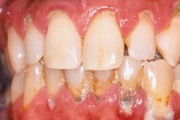

Sümptomid:

- igemed veritsevad (19)

- igemed punetavad (21)

- ige on paistes (mädapunn)

- igemed on tursunud/vohavad (17)

- igemed on valulikud (19)

- puudulik suuhügieen (5)

- igemepealne hambakivi (5)

- igemealune hambakivi (4)